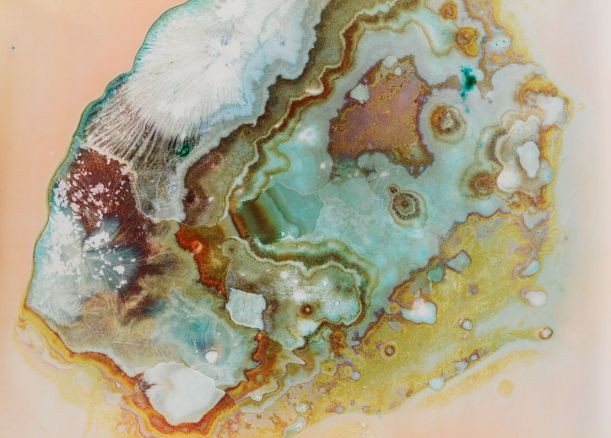

4. Orfiril (valproát sodný)

Používá se k léčbě a prevenci epileptických záchvatů nebo také mánie při bipolární poruše v případech, kdy se tyto stavy nedají léčit lithiem. To ovšem neznamená, že se nedá zneužít.